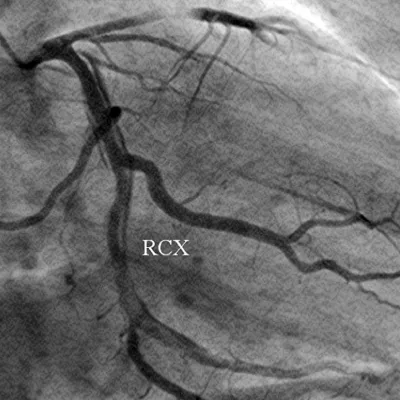

Figure 3: The left coronary artery is shown (right anterior oblique projection) with a long dissection of a large ramus circumflexus (RCX).